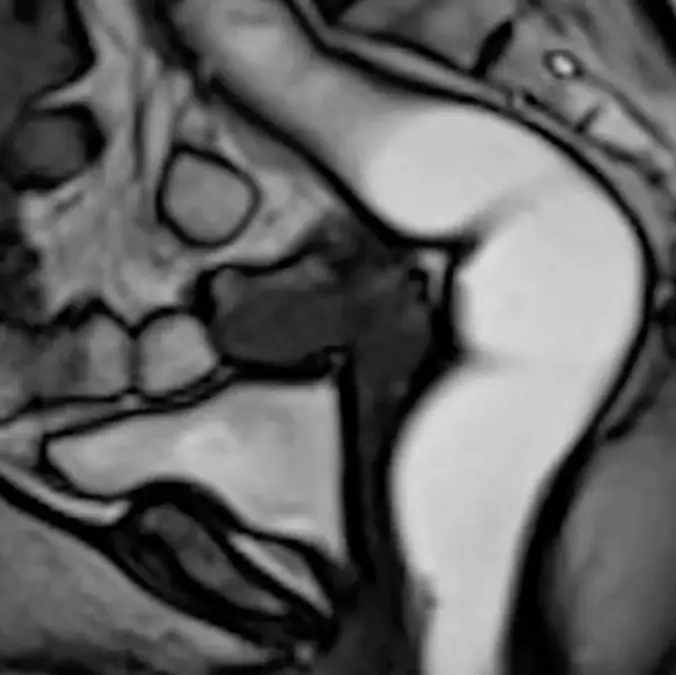

Answering the questions you probably never needed answering, magnetic resonance defecography is used to help doctors identify issues with a patient's rectal function.

Cleveland Clinic explains that defecography in an X-ray machine or an open MRI machine will involve the table tilting vertically, and a custom toilet will be put underneath you.

Using a contrast gel to map the pelvic floor, ultrasound jelly and a catheter are inserted into your back passage while you're placed inside a diaper.

On command, you're told to clench your pelvic muscles in various ways, then eventually pass the jelly – as well as anything else you might need to evacuate from up there.

A fascinating (if a little gross) animation shows things in action, and yep, you can definitely poop inside an MRI scanner.